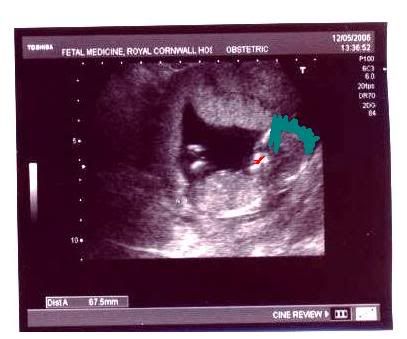

We had the

second scan today, no word as yet on the gender, although and Molly

keep calling Her a He, and as we all know She will be a She until and

only if She decides to be a Boy.

The baby itself, bless her! (anyone else guess I'm hoping for a girl?)

has *Quadrupled* in size, being about 9cm's from foot to head.

She looks to be a natural born soccer player to. Choo called the

movement hiccups, but to me it looked as if she was heading a ball...

My proudest moment was when she kept turning away from the Doctor and

her sonic wand or simply lay resting, as as you can see from the photo

below she has inherited her Father's Smile and Her (Paternal)

Grandfathers restful nature and girth...